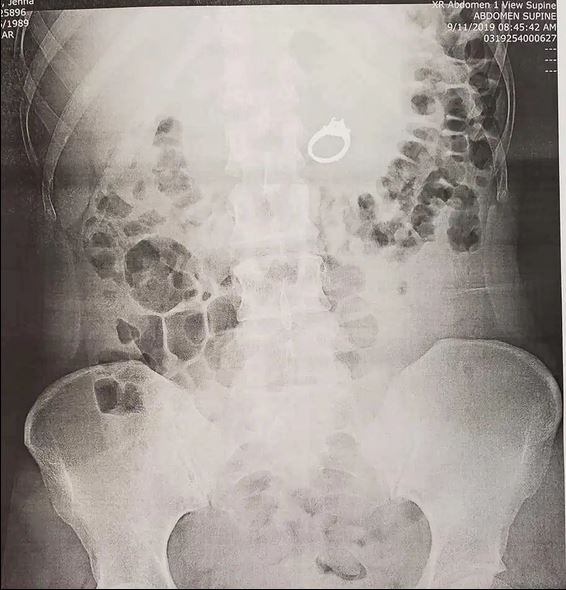

An X-ray showed she had swallowed her own engagement ring

“The doctor ordered an X-ray and seemed pretty shocked when she walked back in with a second doctor and showed me that sure enough, my ring was right there in my stomach!”

Shocking images showed the huge diamond ring in her stomach

Jenna explained the gastroenterologist advised against letting nature take its course and Jenna was sent for an upper endoscopy.